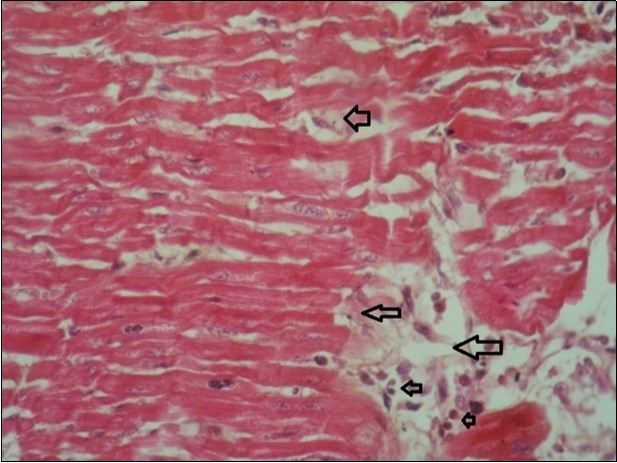

Figure 8.spleen (dead cattle less than 1 year old) showed severe depletion of lymphocytes with necrosis of endothelial lining or splenic arterioles (arrows). (Hematoxylin and fuchsin X 60)

Figure 9.Tongue (dead cattle less than 1 year old) showed vesicular nuclei of stratum corium epithelium which suffering hydropic degeneration. Esinophlic intranuclear inclusions were seen surrounded by hallow zone(arrows). (Hematoxylin and fuchsin X 60)